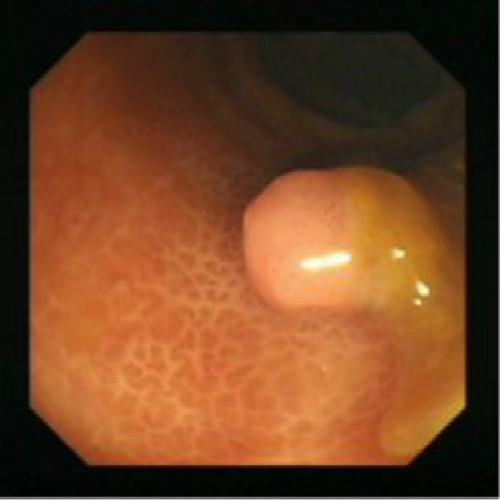

息肉

息肉的